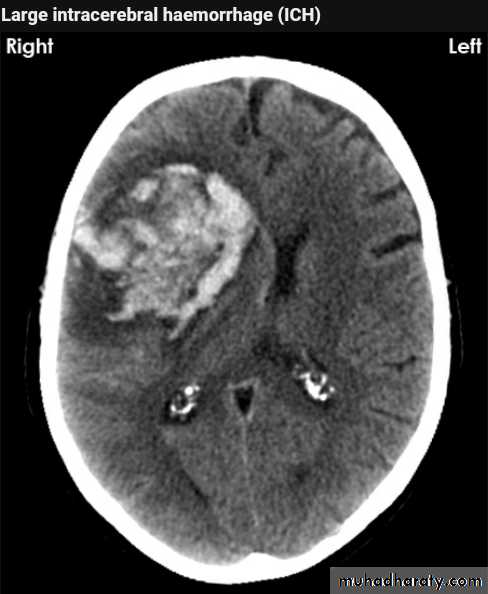

Acute Intra cerebral hematoma

CT finding :Hyper dense area , surrounded by edema , any where within the brain parenchyma.

Shifting of the midline

Compression of the ipsi lateral ventricle .

Associated with infarction , # , trauma concussion , tumor …..